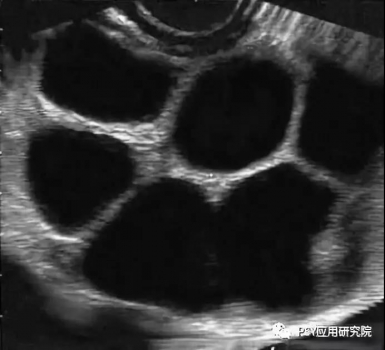

進(jìn)入高溫季節(jié)以后,很多豬場的配懷率開始出現(xiàn)下降,返情率表現(xiàn)上升,屢配不孕的現(xiàn)象有所抬頭,這種情況不僅會導(dǎo)致母豬非正常生產(chǎn)天數(shù)的增加,而且也會降低豬場PSY,那么導(dǎo)致母豬發(fā)生高返情率的原因包括哪些呢? 圖1母豬受孕后出現(xiàn)的不同返情時間 原因之一:發(fā)情鑒定失誤 對母豬進(jìn)行發(fā)情鑒定是人工授精的前提,一旦發(fā)情鑒定失誤,對未發(fā)情的母豬進(jìn)行授精,那么母豬將在配種后的19天之內(nèi)出現(xiàn)返情。 發(fā)情鑒定失敗的原因有二: ➤一方面是由于配種員的經(jīng)驗不夠, ➤另一方面也與母豬的品種與個體發(fā)情表現(xiàn)不明顯有關(guān)。 建議:在每天上午8點和下午5點,每天兩次使用公豬對斷奶母豬和適齡后備母豬進(jìn)行輔助發(fā)情鑒定,加強(qiáng)對母豬發(fā)情表現(xiàn)的辨認(rèn)度,提高發(fā)情鑒定成功率。 圖2 靜立反應(yīng) 原因之二:霉菌毒素污染 在所有霉菌毒素中,玉米赤霉烯酮是對母豬生殖系統(tǒng)危害最為嚴(yán)重的霉菌毒素,它具有類雌激素作用,可促使母豬出現(xiàn)假發(fā)情,但母豬并未排卵,因此配種后又會在很短時間(多發(fā)生19天以內(nèi))出現(xiàn)返情。 建議:豬場加強(qiáng)對飼料原料的控制,尤其是在夏季母豬飼料中應(yīng)降低米糠或麩皮的添加比例,控制貯存時間,可使用膳食纖維等替代品、加強(qiáng)對料槽、料線的清理以及添加霉菌毒素吸附劑的方法來減輕危害。 原因之三:卵巢囊腫 母豬發(fā)生卵巢囊腫以后,由于分泌過多的卵泡素,母豬性欲旺盛,經(jīng)常趴跨其他母豬,但屢配不孕,其原因在于:由于母豬排卵遲滯,精子在母豬排卵之前已喪失受精能力,導(dǎo)致母豬受孕失敗,這類返情多發(fā)生在配種后的19天以內(nèi)。 建議:一旦發(fā)現(xiàn)母豬持續(xù)發(fā)情且屢配不孕,給母豬肌注黃體酮、促黃體素釋放激素或人絨毛膜促性激素,每日1次,連用2-4次。 圖3 卵巢囊腫B超圖 原因之四:精液品質(zhì)下降 使用不合格的公豬精液進(jìn)行輸精,母豬將在19-23天左右出現(xiàn)返情。 這種問題在夏季、秋季高發(fā),研究發(fā)現(xiàn)公豬對熱應(yīng)激高度敏感,在環(huán)境溫度超過30℃以后,無論是精子活力還是精子密度,均會出現(xiàn)明顯下降,造成母豬受孕率大幅下降,而且公豬精液品質(zhì)下降后,其恢復(fù)正常所需時間在2個月左右。 因此建議:夏季必須采取有效措施對公豬進(jìn)行降溫,避免熱應(yīng)激對公豬的不利影響,同時在飼料中添加抗應(yīng)激產(chǎn)品,并控制公豬的使用強(qiáng)度,避免過度使用。 原因之五:輸精時間不當(dāng) 一般而言:母豬在發(fā)情后的24-36h進(jìn)行排卵,排卵持續(xù)時間為10-15h,卵子保持受精能力的時間為8-10h,精子達(dá)到受精部位所需的時間為2-3h,因此最佳的輸精時間為母豬排卵前的2-3h,由于輸精時間不當(dāng)而導(dǎo)致的返情多發(fā)生在配種后的19-23天。 建議:在無試情公豬條件下,可采用下表進(jìn)行人工授精。 原因之六:子宮復(fù)舊不全 研究發(fā)現(xiàn):母豬在分娩過程中,無論是順產(chǎn)還是助產(chǎn),子宮都會有不同程度的損傷,子宮復(fù)舊不全將導(dǎo)致母豬出現(xiàn)返情,一般發(fā)生在配種后的19-23天。 為確保子宮復(fù)舊完全,需要做到以下三點:盡量避免掏產(chǎn),加強(qiáng)母豬產(chǎn)后護(hù)宮,在母豬產(chǎn)后使用宮炎凈,促進(jìn)子宮黏膜修復(fù)和生長;給予足夠的復(fù)舊時間,確保泌乳時間不低于19天;配懷舍溫度控制在24℃左右,給母豬創(chuàng)造良好條件。 圖4 子宮復(fù)舊良好的母豬 原因之七:飼養(yǎng)管理不當(dāng) 母豬在配種后的30天之內(nèi)是胚胎死亡的高峰期,造成胚胎死亡的原因包括:各種應(yīng)激(熱、冷、噪音、驚嚇、免疫、驅(qū)蟲)、飼喂過多或過高能量飼料,研究發(fā)現(xiàn):母豬建立穩(wěn)定的妊娠狀態(tài)至少需要5枚胚胎,低于這個數(shù)量將導(dǎo)致母豬在懷孕后的19-23天出現(xiàn)返情。 建議:在配種后的30天內(nèi),對母豬進(jìn)行嚴(yán)格限飼,并添加青綠飼料或膳食纖維,采用“六不一優(yōu)”技術(shù),在配種的30天母豬飼喂量控制1.8-2.2kg左右,減少各種應(yīng)激,保持配懷舍安靜和涼爽,并在飼料中添加生殖營養(yǎng)(如:仔多多),可促進(jìn)母豬分泌子宮乳和胚胎著床,減少胚胎死亡。 圖 5 “六不一優(yōu)”技術(shù) 原因之八:疾病因素 目前豬場導(dǎo)致母豬出現(xiàn)返情的主要疾病包括:藍(lán)耳病、偽狂犬、豬瘟、細(xì)小病毒、乙腦等。尤其是夏季高溫季節(jié),在懷孕中期出現(xiàn)的流產(chǎn),乙腦、細(xì)小病毒是需要重點關(guān)注的致病原。 建議:豬場每年需檢測藍(lán)耳病、偽狂犬、豬瘟等主要疾病抗體水平;每年4月底之前對所有種豬普免乙腦,對第一胎、第二胎母豬普免細(xì)小病毒疫苗。 小結(jié): 豬場應(yīng)在母豬配種后的21天,使用B超進(jìn)行妊娠鑒定,母豬發(fā)生返情以后,需要記錄返情發(fā)生時間、返情比例,根據(jù)其返情規(guī)律確定其可能的原因,再采取對應(yīng)的措施,方能將返情率控制在8%以下比較合理的水平。 原創(chuàng): 劉輝旺 來源:PSY應(yīng)用研究院 |